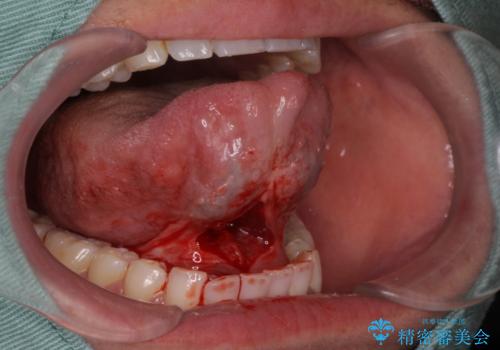

- 滑舌が悪く舌小帯を切りたいとの事で来院。

舌小帯切除術を行いまいした。

- 外科手術のため、術後に出血、痛みや腫れ、違和感を伴います